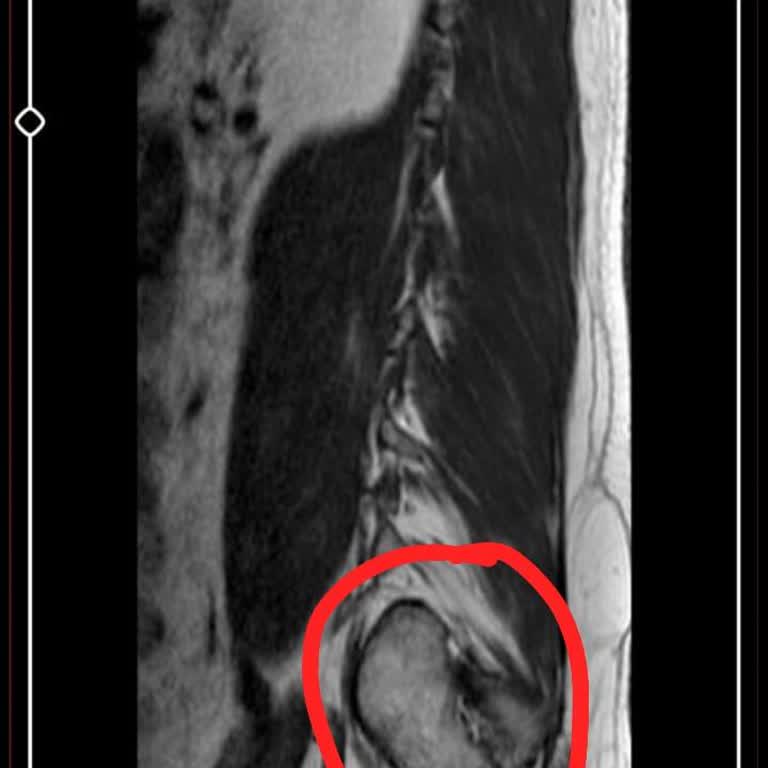

Şahsım 43 yaşında Emekli olup, Elazığ'da ikametgah etmekteyim. Bel fıtığı ağrılarımdan dolayı Kayseri Dr. Ö**** A******* kliniğinde robotik lazer ve nokta atışı tedavisi gördüm. Ağrılarım tedaviden sonra aşırı arttığı için ikametgahım Elazığ'da şehir hastanesinde ameliyat olmak zorunda kalarak, şifa...